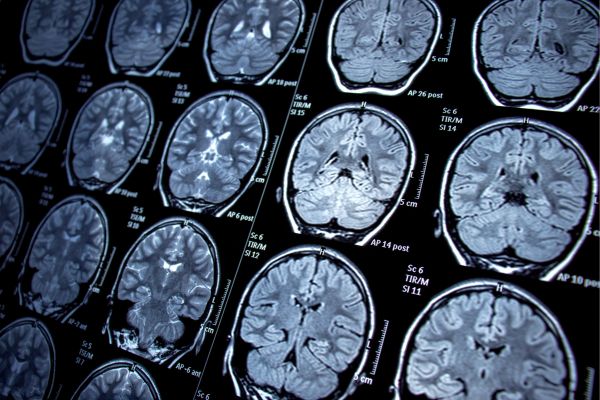

Екип от Детския изследователски институт „Мърдок“ и Кралската детска болница в Мелбърн, Австралия, разработва усъвършенстван инструмент с изкуствен интелект, който открива малки мозъчни лезии, причиняващи тежка епилепсия при деца. Чрез него диагностицирането е по-бързо, а лечението по-прецизно.

Екипът, чийто ръководител е д-р Ема Макдоналд-Лорс, нарича създадения от него и усъвършенстван с изкуствен интелект детектор „детектив на епилепсия с изкуствен интелект“. С помощта на образната диагностика той открива лезии (фокални кортикални дисплазии) с размерите на боровинка и дори по-малки от нея в 94% от случаите.

За обучението на детектора учените използват ЯМР и FDG-PET сканирания (позитронно-емисионна томография).

Както пояснява ръководителката д-р Ема Макдоналд-Лорс, причините за епилепсията са различни, но при три от десет случая тя се дължи на структурни аномалии в мозъка. И тъй като става дума за изключително малки лезии, които са скрити дълбоко в мозъчните гънки, те често биват пропускани при ЯМР.